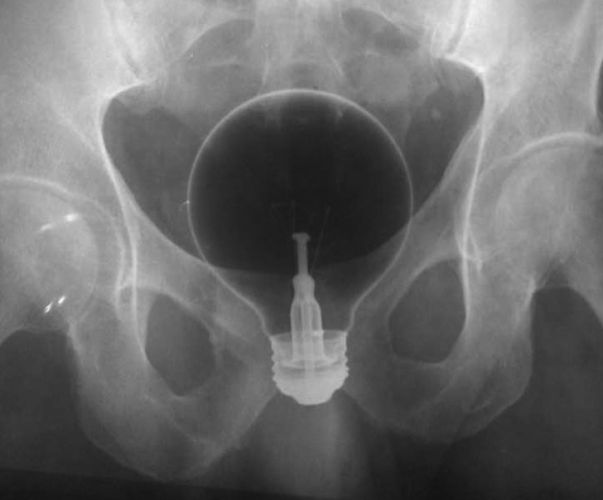

Os objetos mais BIZARROS encontrados no ânus pelos médicos